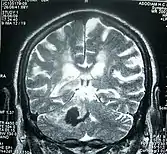

Perinatal stroke can be diagnosed with medical imaging techniques that present the brain's image. The usage of diffusion-weighted imaging with magnetic resonance imaging is effective for early diagnosis of perinatal stroke.[18] Computerized tomography (CT) is also a commonly used diagnostic technique for this disease.[35] These medical imaging techniques can show bleeding or blockage in the brain and detect damage caused by ischemic stroke or hemorrhages to the brain tissues.[36] Magnetic resonance imaging is clinically preferred to computerized tomography as it can highlight the brain's blood flow.[35] In addition, perinatal stroke is challenging to classify on computerized tomography as the neonatal brain has higher water content.[7][36] However, in certain situations, such as the inability to transport unstable infants with severe respiratory or cardiac disorders from the intensive care unit, cranial ultrasound is used as an alternative to magnetic resonance imaging.[7] Cranial ultrasound can identify intracranial hemorrhage, intraventricular hemorrhage, large cerebral sinus venous thrombosis along with the brain's blood flow.[7]